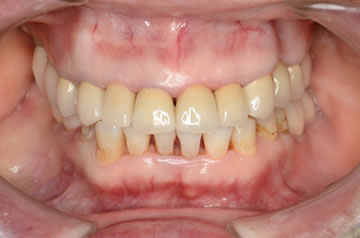

治療後のレントゲン、口腔内写真です。

奥歯すべてにインプラント治療を行いました。歯周基本治療をおこない歯肉の発赤もなく、PCR20パーセント以下、BOP9パーセント以下です。

綺麗な口腔内になりました。